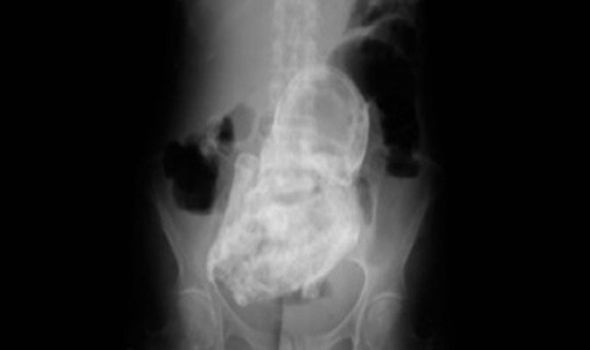

На рентгеновском снимке видны кости, череп, ребра, руки, ноги и позвоночник ребенка.

Данная аномалия, при которой плод "окаменевает" носит название lithopedion, чаще всего случается при внематочной беременности. В медицинской литературе насчитывается не более 300 подобных случаев. Это происходит когда плод умирает, но эмбрион является слишком большим, чтобы быть поглощенным телом. Плод уже сформировался и является для организма слишком большим для поглощения телом. Далее плод кальцифицируется (окаменевает) снаружи, чтобы уберечь мать ребенка от заражения.